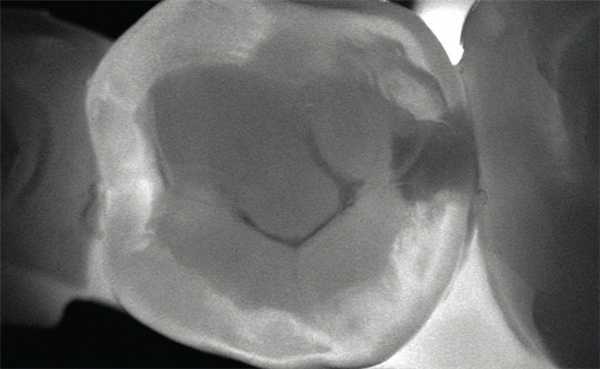

Рис. 1. При обследовании контактного пункта зубов 26, 27 (нижний фрагмент) кариес визуально не определяется; на сагиттальном реформате компьютерной томограммы в области проксимальных к контактному пункту поверхностей тех же зубов деминерализация очевидна.

Для диагностики кариеса существует множество методик — от простого осмотра полости рта до применения суперсовременной лазерной технологии DIAGNOcam (рис. 2).

Рис. 2. Сохраненное изображение просвеченного зуба, полученное при обследовании с помощью KaVo DIAGNOcam.

В связи с отсутствием эффекта суммации структур, через которые проходит луч при обычном лучевом исследовании, на компьютерной томограмме можно обнаружить мельчайшие очаги деминерализации, неопределяемые с помощью внутриротовой камеры и невизуализируемые на интерпроксимальных снимках (рис. 1).